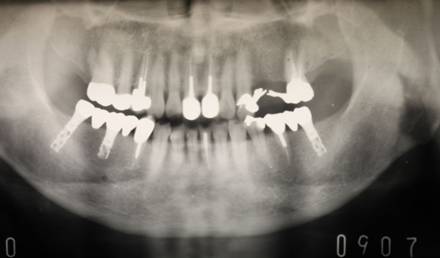

治療後。歯周病で失われた骨が回復しています。使用インプラントはスプラインツイストです。

上部構造装着後6年。ハイブリッドレジンを使用したため、少し艶がなくなってきました。上部構造の材料には金属、ハイブリッドレジン、セラミックなどがあります。セラミックはきれいですが欠けやすいため、最近はフルジルコニアを使っています。

インプラント装着後6年。順調に経過しています。12か月毎のメインテナンスをしています。